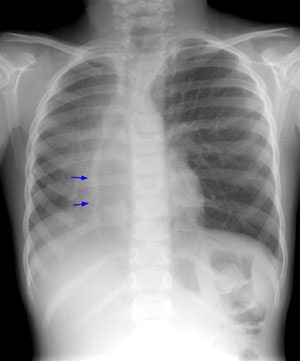

Scimitar Syndrome:

In Scimitar syndrome the heart and mediastinum are shifted towards the involved side (dextropositioning of the heart in this case) due to the pulmonary hypoplasia. There is compensatory overexpansion of the opposite lung. The thoracic cage is smaller on the affected side with approximation of the ribs, although this may not be evident at birth. The anomalous draining vein produces a curvilinear vascular shadow which courses towards the hemidiaphragm and has the appearance of a Turkish sword (or scimitar- blue arrows). A retrosternal opacity may be seen on the lateral exam (yellow arrows). This density has previously been erroneously ascribed to extrapleural areolar tissue anterior to the visceral pleura of the right lung. In actuality, this density is produced by the interface of the displaced mediastinum with the aerated, small right lung.Click on small images to enlarge